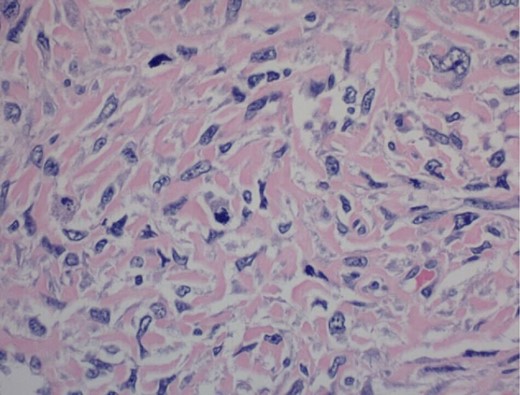

Pathology report was significant for mitotic figures on hematoxylin and eosin stain (Fig. 4). Immunohistochemistry showed actin positivity (Fig. 5) and desmin positivity (Fig. 6) in the tumor cells. All lymph nodes and margins were negative, with the smallest margin measuring 1.5 cm. The findings listed in the pathology report were consistent with primary leiomyosarcoma of the small bowel.

400× magnification. Hematoxylin and eosin stain of tumor cells showing mitotic figures.

It is extremely difficult to differentiate between leiomyosarcoma and GIST, as many of the tumors present uniquely and symptoms and appearance of the tumor can vary [6]. The tumors are definitively diagnosed with histopathology and immunohistochemistry, with leiomyosarcoma showing actin and desmin positive reactivity consistent with smooth muscle cell origin and CD117, CD34, PDGFRA, and DOG1 negativity [3].